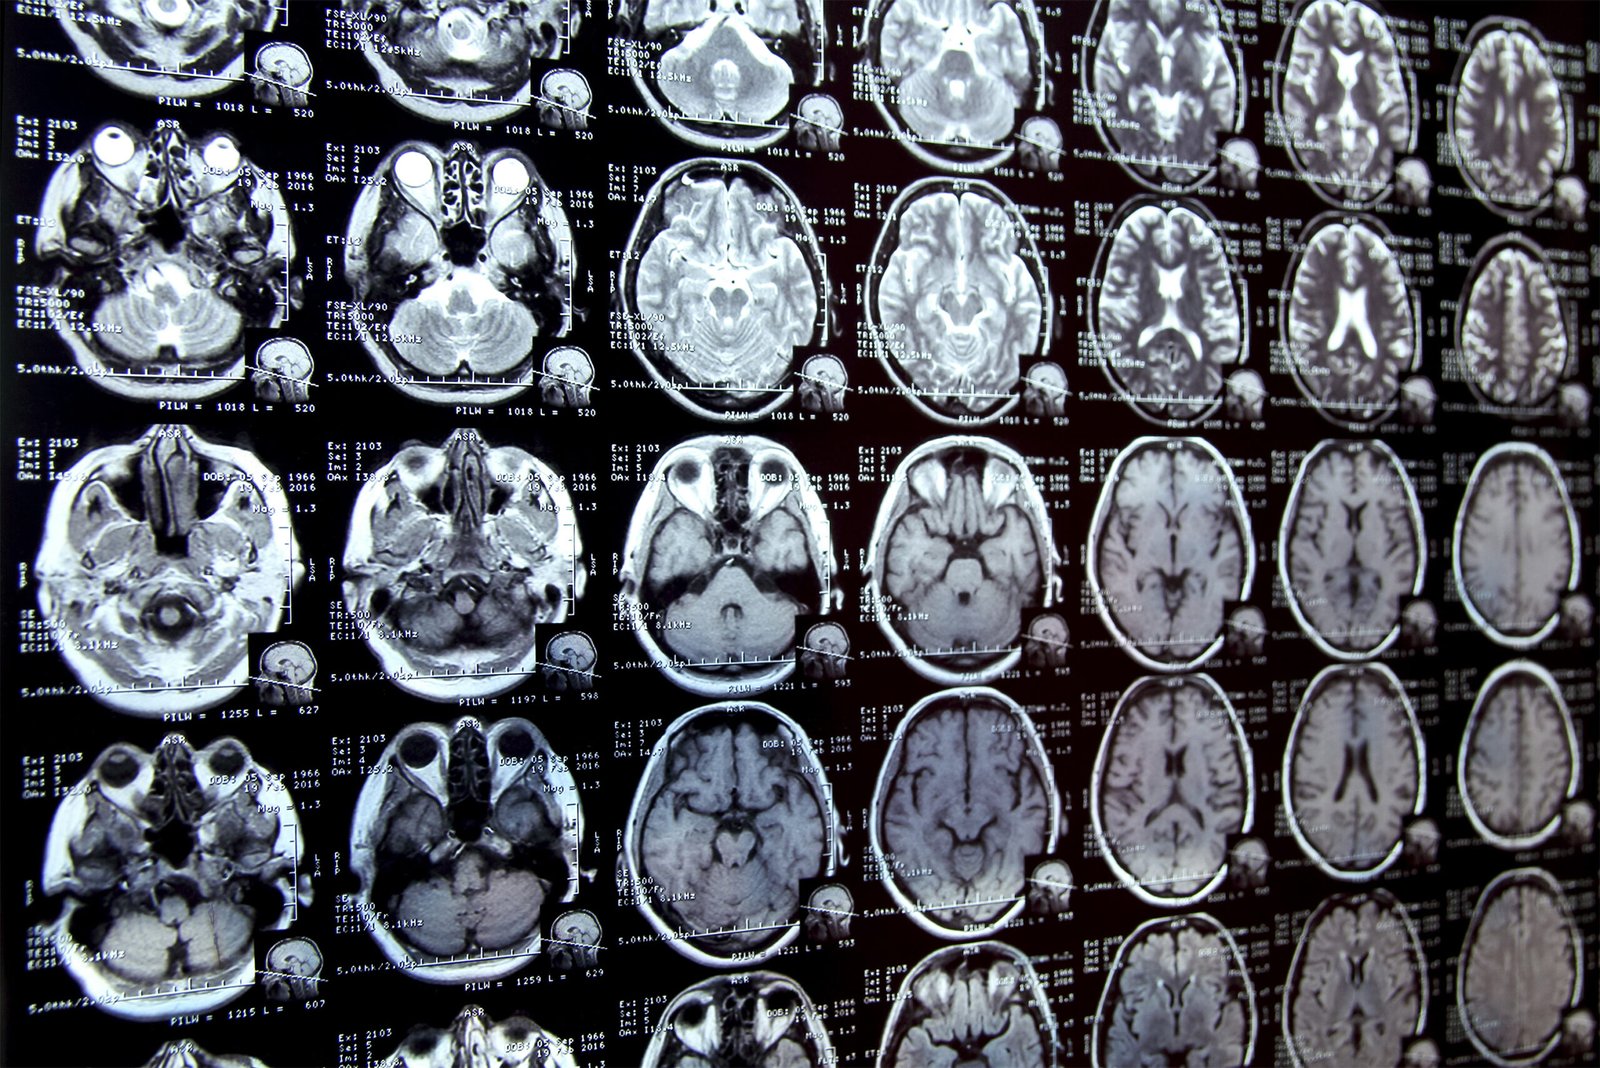

Annotating regions of interest in medical images, a process known as segmentation, is often one of the first steps clinical researchers take when conducting a new study involving biomedical images.

For example, to determine how the size of the brain’s hippocampus changes as patients age, the scientist first describes each hippocampus in a series of brain scans. For many structures and image types, this is often a manual process that can be time-consuming, especially if the regions being studied are difficult to delineate.